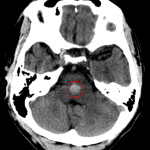

Age: 61

Sex: Female

Indication: Right side weakness

Findings

- Round area of hyperdensity in the mid pons with minimal surrounding hypoattenuation

- Sequela of chronic small vessel disease

- Age-advanced global cerebral atrophy

- Atherosclerotic calcification of the cavernous internal carotid arteries

Diagnosis

- Hypertensive hemorrhage

Acute hemorrhage in the mid pons, likely hypertensive in etiology given location. Minimal surrounding edema without significant mass effect. No intraventricular extension, hydrocephalus, or evidence of herniation.

Sequela of chronic small vessel disease. Age-advanced global cerebral atrophy. Intracranial atherosclerosis.